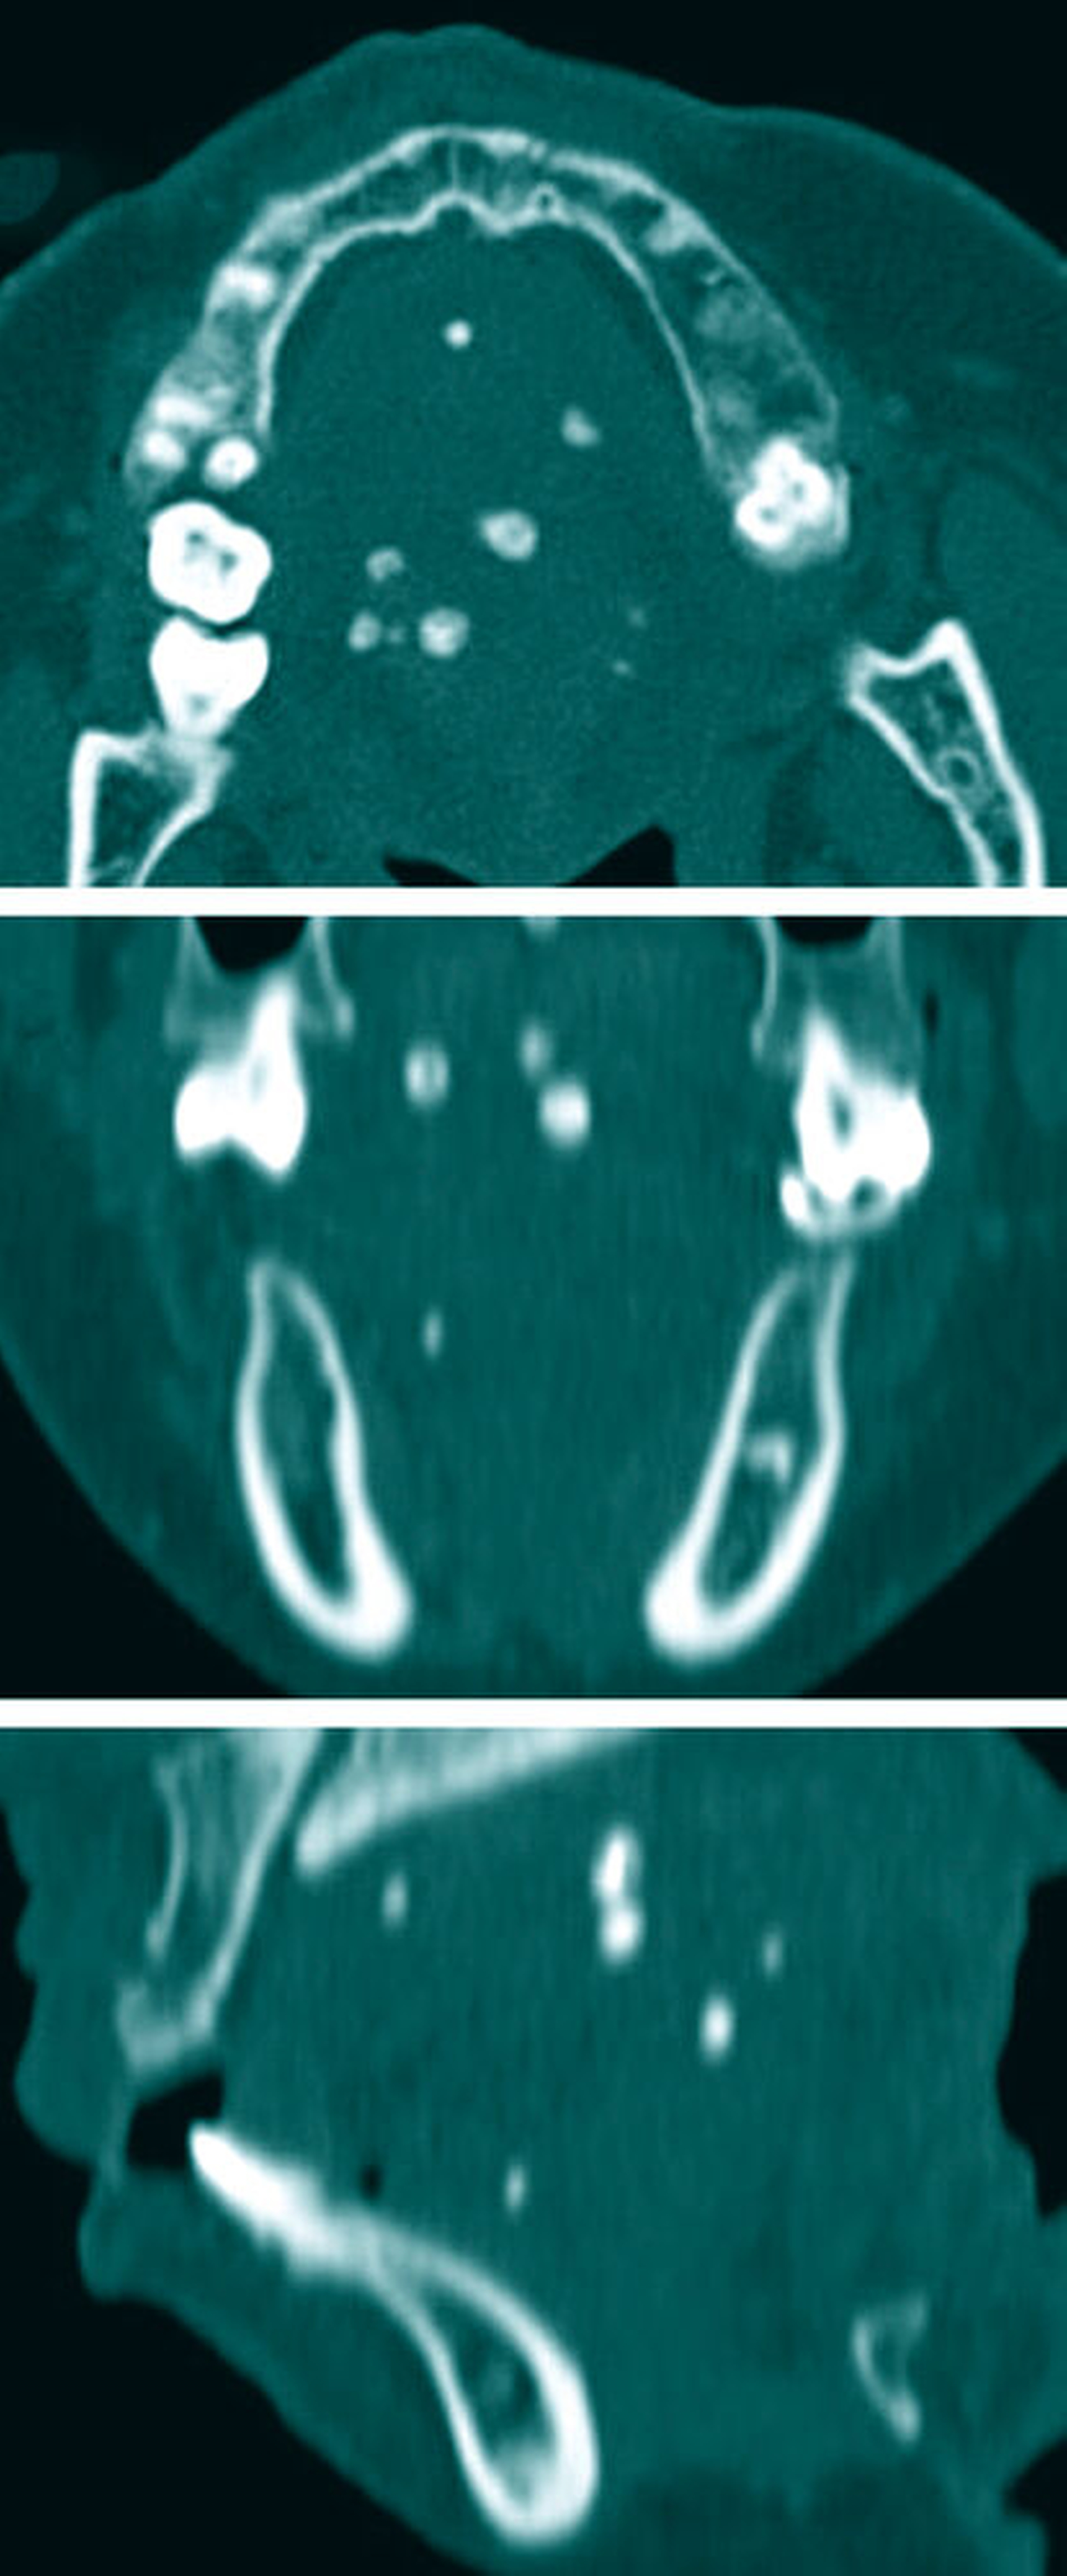

Im Orthopantomogramm (Abbildung 2) stellten sich neben dem aktuellen Zahnstatus zwei rundliche Verschattungen apikal des Zahnes 23 sowie in der Nähe des linken Foramen mentale dar. Das Angio-CT (Abbildung 3) ergab im posterioren Bereich des Zungenkörpers eine Hypervaskularisierung, die bei einer maximalen Abmessung von 2,7 cm x 3,5 cm x 4,8 cm multiple rundliche Verkalkungen im Sinne von intravasalen Phlebolithen einer vaskulären Anomalie aufwies.